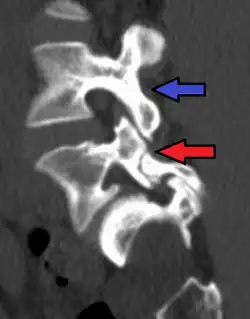

Red arrow brake in pars interarticularis. Blue arrow normal pars interarticularis. Spondylolisthesis at L5.

X-rays (electromagnetic radiation) are projected through the body to produce an image of its internal structures. The radiation is more attenuated (absorbed) by the denser tissues of the body (i.e. bone) than the softer tissues (i.e. muscles, organs, etc.) creating a picture composed of shades of grey ranging from white to black. A vertebra with a fracture or defect of the pars interarticularis will have a dark mark through this region of bone. Since this is difficult to see on the AP (anterior posterior) x-ray view an oblique x-ray of the lumbar spine can usually identify the spondylolysis. If inconclusive a further CT scan can produce a 3-dimensional images to more clearly show the defect although the exam increases the patients radiation dose by at least an order of magnitude than plain x-rays.[16][17]